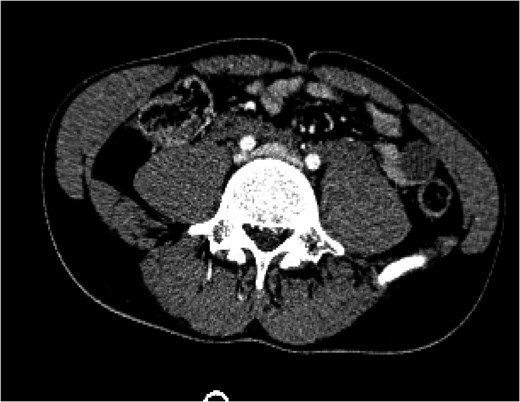

Figure 1:

A CT of the abdomen and pelvis taken on arrival (Day 1) showed a blush of contrast at the bifurcation of the common iliac veins.